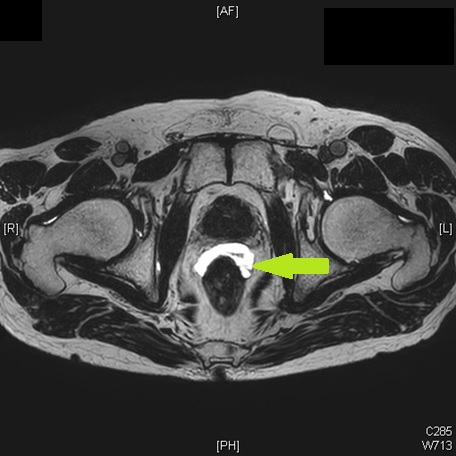

泌尿器科とともに、I-125シードを用いた前立腺癌小線源治療を年20-30例程度行っています。腰椎麻酔下で3泊4日の入院となります。

スペーサゲル